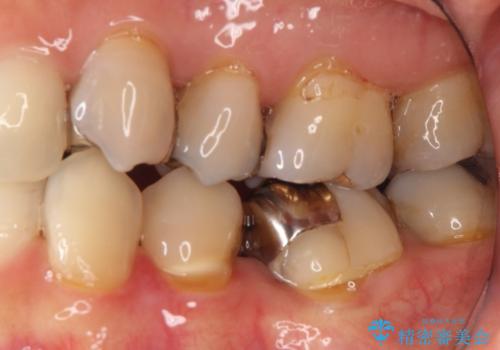

- 定期健診にて虫歯が見つかった患者さんです。県外からお越しいただいている事もあり、かなりお久しぶりの来院でした。歯と歯の間のところと銀歯の下が虫歯になっていました。被せ物はオールセラミッククラウンで治療しました。

銀歯を外すとかなり大きな虫歯になっていました。幸いぎりぎりのところで神経まで虫歯は広がっていなかったため、症状が出ない事を確認した後、オールセラミッククラウンで治療しました。虫歯除去後、残っている歯質が少なかったため、破折抵抗を考慮し部分的な被せ物ではなくクラウンを選択しました。